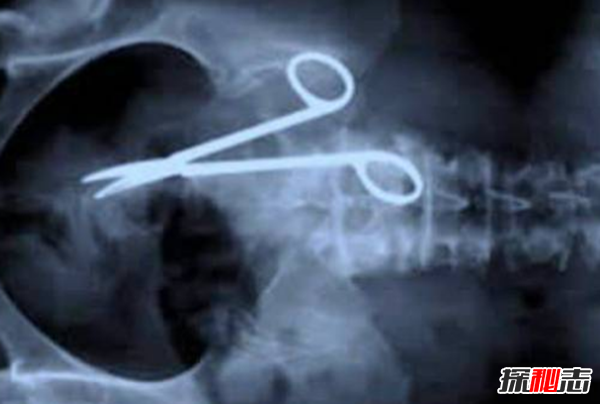

4、剪刀

当澳大利亚人帕特·斯金纳在手术18个月后回到医院,抱怨胃痛,医生们发现了一年多前失去的东西——他们的外科剪刀!